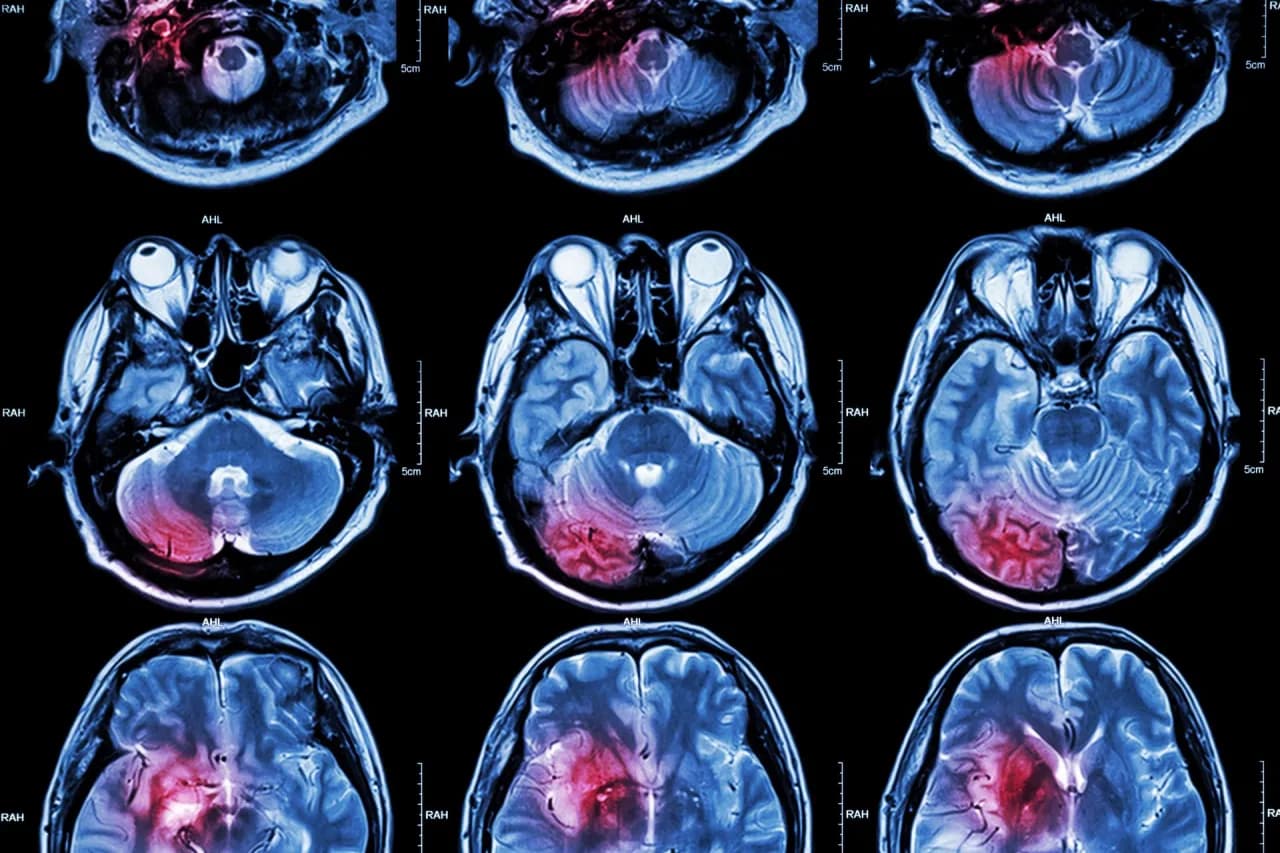

Udar mózgu to nagłe zaburzenie krążenia krwi w mózgu, które może prowadzić do poważnych uszkodzeń. Jaki udar jest gorszy: prawostronny czy lewostronny? Odpowiedź zależy od lokalizacji uszkodzenia. Udar prawostronny dotyka prawej półkuli mózgu, odpowiedzialnej za zdolności przestrzenne i emocjonalne, podczas gdy lewostronny wpływa na lewą półkulę, która kontroluje mowę i logiczne myślenie.

Różnice między tymi typami udarów są znaczące. Udar prawostronny często powoduje problemy z percepcją przestrzenną i rozpoznawaniem twarzy, natomiast lewostronny może prowadzić do afazji, czyli zaburzeń mowy. Każdy z nich wymaga innego podejścia w leczeniu i rehabilitacji.